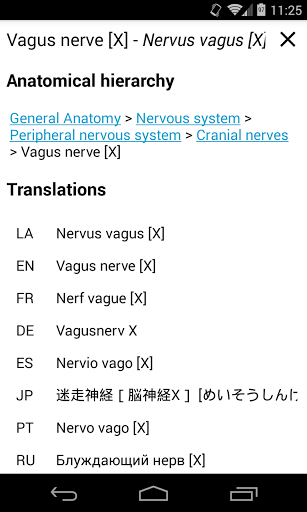

-In the details view of an anatomical structure related terms are now displayed

-Updated japanese translations

-The Korean language is now available for the app and the anatomical structures.

-New language: Italian